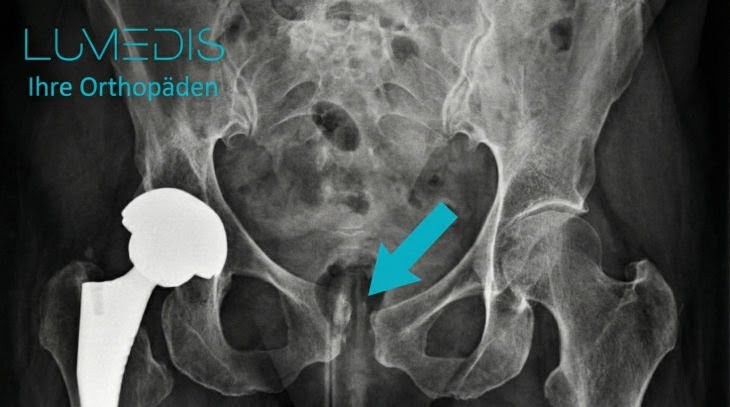

Röntgenbild einer Symphysenspregung

Nebenberuflich erkennt man eine Hüftprothese auf der rechten Seite des Patienten.

Der türkise Pfeil links zeigt auf die Symphyse, der rechte Pfeil zeigt auf die Symphysensprengung.